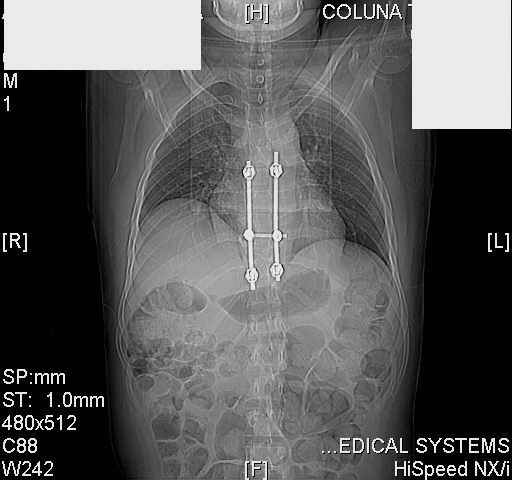

dear all (George?) Got a note this morning requesting an opinion about a patient 25 yrs froma remote area of the country who received this "excellent" stabilization of a fracturedthoracic spine over a year ago.The original neurosurgeon liberated the patient for fullactivities and rehab etc.The rehab doc wants to know what to do. Looks to me like the patientwas screwed pretty good! any offers?

Tom, Harrington rods from a medical museum, with industrial strength screws from a boatbuilder. What are the current symptoms?

Interesting case. Findings on CT: all four pedicle screws have been placed improperly inthat they miss the vertebral bodies. In addition, the screws on the left side are impingingon the decending thoracic aorta. What I do NOT know is the nature of the original injury, orwhether or not that injury has resolved. I would recommend removal of the hardware. I don'tthink it's a good idea to leave those screws where they are. If the original fracture ishealed, nothing else needs to be done.